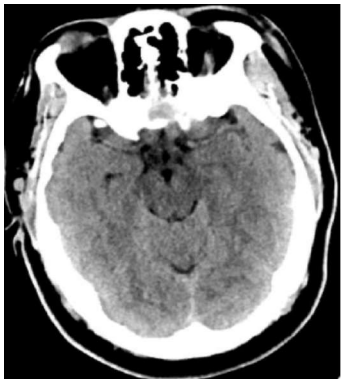

Uma mulher de quarenta anos de idade, obesa, hipertensa e tabagista, em uso irregular de hidroclorotiazida e anticoncepcional oral, compareceu ao pronto-socorro, queixando-se de cefaleia súbita de forte intensidade, iniciada há cerca de 12 h e associada a episódio de vômito. Refere que apresentou episódios semelhantes nas últimas duas semanas, de menor intensidade. Realizou a tomografia de crânio mostrada a seguir.

Internet: © 2017 Elliot K. Fishman, MD.

Com base nesse caso hipotético, assinale a alternativa que apresenta a conduta a ser adotada inicialmente.